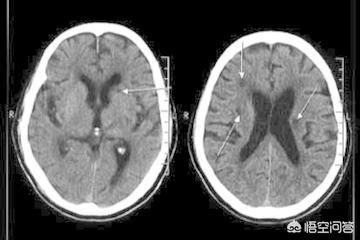

2.海綿状梗塞の割合は年齢と密接な関係があり、60歳以上の人がCTを受けると50%以上の人に海綿状梗塞巣(低密度の影)が見つかり、70歳以上の人の80%以上に海綿状梗塞巣が見つかり、時には複数の海綿状梗塞巣が見つかり、80歳以上の人の大部分には複数の海綿状梗塞巣があります。したがって、脳血栓症がなければ、脳梗塞(小さな動脈プラーク破裂血栓症、梗塞の大きさは海綿体梗塞よりはるかに大きい)は脳動脈終末の老化によるものと考えることができる。一方、30〜50歳の若年層では、海綿体梗塞の割合が高いことが判明している。そのほとんどは、感情的なストレスによって小さな脳動脈が痙攣し、わずか4〜6分で脳細胞が不可逆的に死滅することに関係している。

多くの高齢者は、病院でCTを撮った後、診断書に「脳梗塞」と書かれているのを目にする。脳梗塞」という文字を見た途端、恐怖を感じずにはいられなくなり、慌てて医師に尋ねる。私は脳梗塞なのでしょうか?

ラクナ脳梗塞で閉塞する血管は非常に細いため、脳組織の損傷はほとんどなく、臨床症状も非常に軽いことが多い。ほとんどの患者には臨床症状がなく、めまい、頭痛、手足のしびれ、めまい、記憶障害、反応速度の低下、認知症などの症状がみられるのはごく少数である。発症率からみると、年齢が高くなるにつれて、ほとんどすべての高齢者がラクナ脳梗塞を発症するようになる。

確かにラクナ脳梗塞の方の中には、全く具合が悪くなく、脳梗塞の症状があったことも覚えていない方もいらっしゃいますが、通常、ラクナ脳梗塞の病変は、他の理由でCTやMRを撮って初めて脳内に発見されます。この場合、神経内科では「無症候性脳梗塞」と呼んでいます。これは、画像で検出されたものの臨床的に症状のない梗塞は、たいていサイズが小さかったり、機能に影響する部位になかったりすることを意味する。この現象は高齢者では珍しくない。